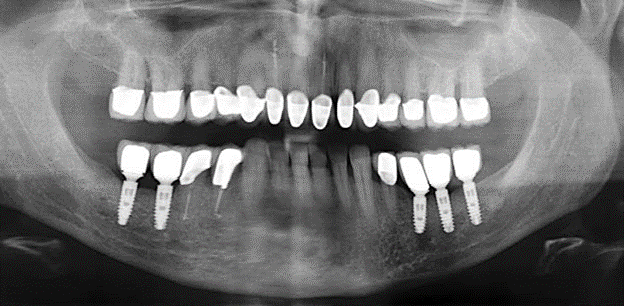

Fig. 1: Panoramic radiograph of initial situation in 2004.

A 52-year-old patient presented in our clinic for the first time in 2004 following tooth loss in the third quadrant, expressing a desire for a new prosthetic restoration. Periodontal and radiological diagnostics revealed the need for extensive periodontological treatment. In addition, teeth 48, 28 and 27 were attributed a very poor prognosis and were subsequently extracted (Fig. 1). Following the successfully completed, systematic periodontological treatment, a fixed dental implant was inserted with the introduction of five implants in tooth regions 35, 36, 37, 46 and 47. Prosthetic treatment of the natural teeth was effected with veneered zirconium dioxide ceramic crowns; the implants were composed of two-piece, individual zirconium dioxide abutments and similarly veneered crowns made of a zirconium dioxide ceramic (Cercon base colored, Dentsply Sirona Lab). Definitive insertion of the prosthetic restoration occurred in 2005.

The ten-year check-up revealed no indications of advancing clinical attachment loss or peri-implant bone substance loss (Fig. 3).

Fig. 3: Panoramic radiograph after ten years with implants.